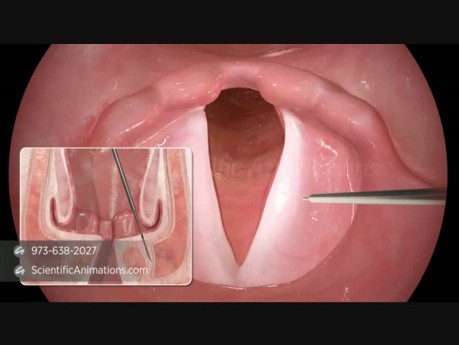

Animacja 3D - rekonstrukcja strun głosowych

Animacja przedstawia zabieg rekonstrukcji struny głosowej. Przy zastosowaniu bio implantu można leczyć zarówno jedno- jak i obustronne porażenie strun głosowych.